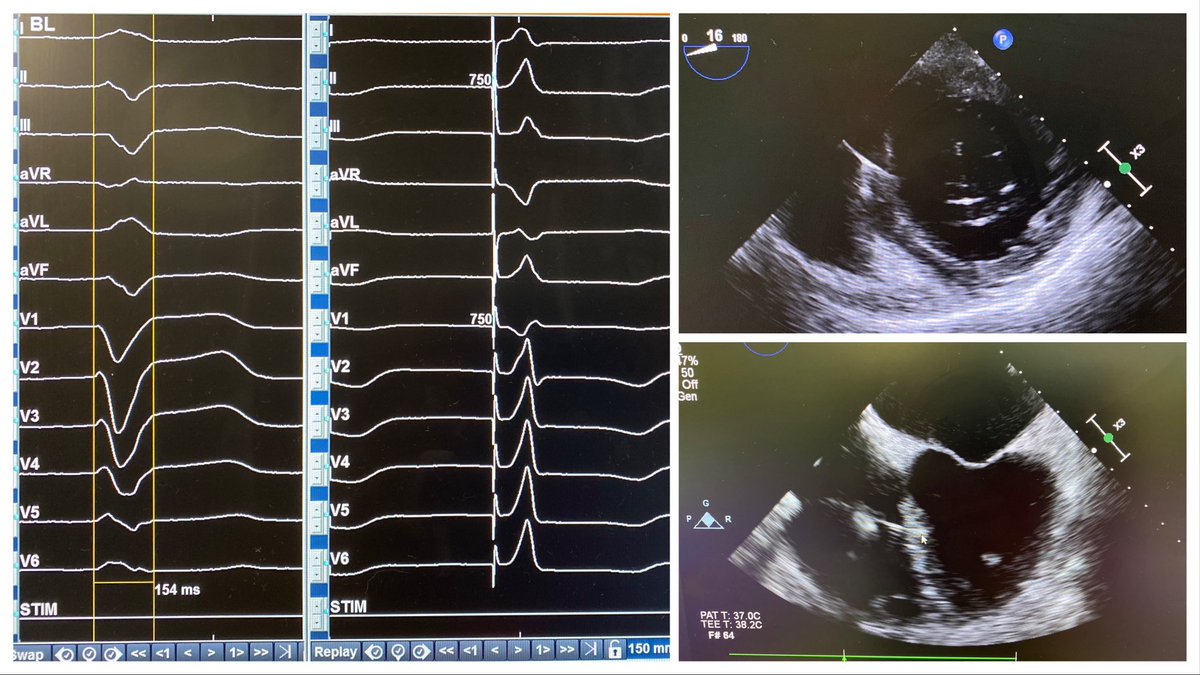

Can you guess what happened during echo? Hint: no meds involved

#echofirst#cardiotwitter pic.twitter.com/07WDqleE5w -

Dilated CM, AF w/

RV pacing ->PM lead extraction & upgrade to CRT. Native LBBB w/ rate & output dependent recruitment at His, went deep septal -> 0.6V threshold, QRS 106ms. Amazing field and techniques we have. #EPeeps#Cardiotwitter#dontdisthehis pic.twitter.com/D9E4jTanyz